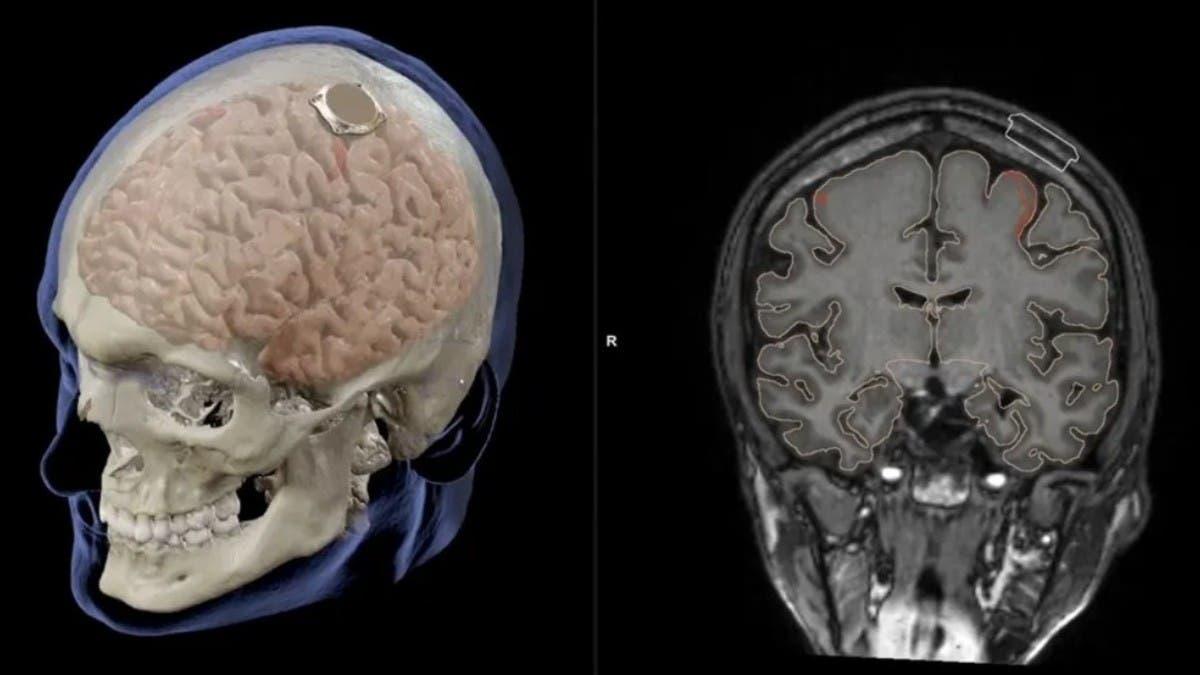

شهدت تكنولوجيا الشريحة المزروعة في الدماغ تطوراً مذهلاً في السنوات الأخيرة، حيث بات من الممكن تحويل إشارات الدماغ العصبية إلى نصوص مكتوبة بدقة متناهية. تعتمد هذه التقنية على مبدأ قراءة النشاط الكهربائي في مناطق محددة من الدماغ مرتبطة باللغة والتفكير، ومن ثم ترجمتها إلى كلمات مفهومة عبر أنظمة الذكاء الاصطناعي المتقدمة. الهدف الرئيسي من هذه التقنية هو تسهيل التواصل لدى الأشخاص الذين يعانون من صعوبات حركية أو فقدان القدرة على التعبير، مما يفتح آفاقاً جديدة لعلاج الحالات العصبية المختلفة.

كما أن الأبحاث الحالية تركز على تقليل الأضرار الجانبية وضمان أمان النظام على المدى الطويل، مما يجعل من هذه التقنية حلاً واعداً لعالم المستقبل، حيث تصبح الأفكار جزءاً مباشراً من عملية التواصل الإلكتروني.